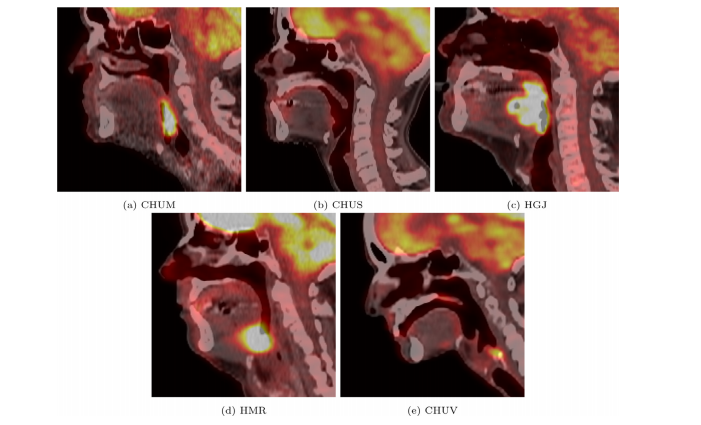

Fig. 1. Case examples of 2D sagittal slices of fused PET/CT images from each of the five centers. These images are obtained after resampling the PET image and the CT image to 1×1×1 mm3 with a tricubic interpolation. The CT window in Hounsfield unit is [−140, 260] and the PET window in SUV is .

图 1. 来自五个中心的融合PET/CT图像的2D矢状切片案例示例。这些图像在将PET图像和CT图像重新采样到1×1×1 mm³,并使用三次立方插值后获得。CT窗口的赫氏单位为[−140, 260],PET窗口的SUV为。